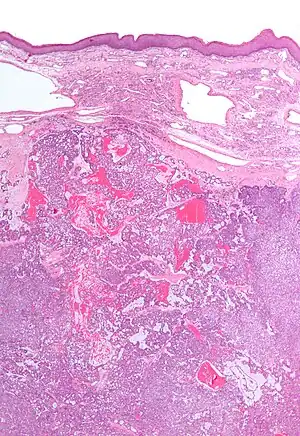

Low magnification micrograph of a polymorphous low-grade adenocarcinoma, showing the typical variation of architectural arrangement. H&E stain.

• It has a varied microscopic architectural appearance, i.e. it is polymorphous.

PLGAs consist of a monomorphous cell population that has a varied histologic morphology.

Microscopically, its histology can be confused with an adenoid cystic carcinoma and a pleomorphic adenoma.